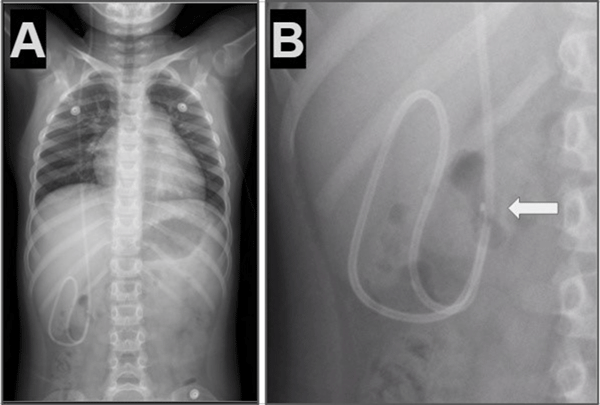

Caso 1. Paciente masculino de 6 años con antecedentes de hidrocefalia secundaria a hemorragia intraventricular del prematuro y colocación de DVP a los 9 meses de vida que presentó cuadro clínico de 12 horas de evolución caracterizado por cefalea, vómitos y somnolencia. Tomografía de cerebro evidenció dilatación del sistema ventricular respecto a estudios previos. Radiografías de recorrido del sistema mostraron la migración retrógrada del catéter distal (Figura 1).

Figura 1. Caso 1: A) Se observa en Rx de tórax y abdomen (frente) catéter distal a nivel abdominal con migración retrógrada. B) Magnificación de Rx de abdomen que evidencia catéter en doble caño con signo radiológico del “caño de escopeta” o “signo del anzuelo” (flecha blanca).